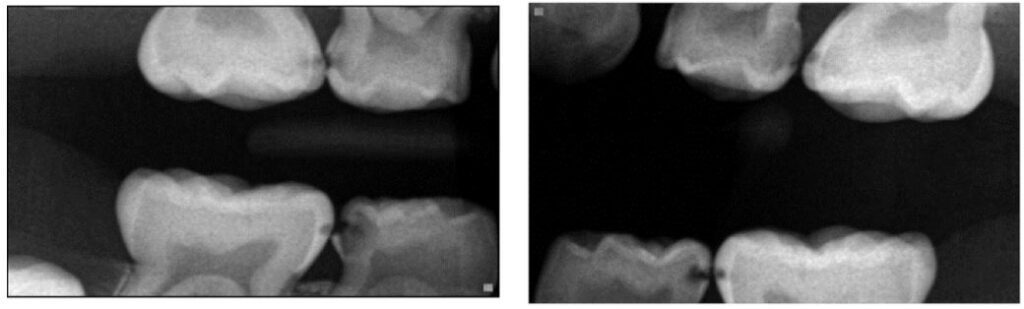

Loại hình sâu răng thứ hai ảnh hưởng đến phần lớn trẻ em là sâu kẽ, liên quan đến mặt xa R4 sữa và mặt gần R5 sữa (Hình 3).

70% sâu răng ở trẻ là thuộc nhóm LCC. Trẻ bị sâu LCC nghiêm trọng thường đặc trưng bởi tình trạng răng chen chúc, thiếu khoảng các răng sau. Sự đóng khoảng sinh lí giữa R4 và R5 sữa xảy ra vào tầm 4 tuổi.

Phân biệt LCC với ECC chủ yếu dựa vào tổn thương trên R4 sữa. Ở LCC, sâu răng bắt đầu từ mặt tiếp xúc, tiến triển dần làm các sườn múi bị phá hủy, lúc đó sẽ nhìn thấy được từ mặt nhai. Với ECC, sâu răng ở R4 sữa xuất phát từ mặt nhai, lan rộng sang phía bên, ngược lại hoàn toàn với LCC.